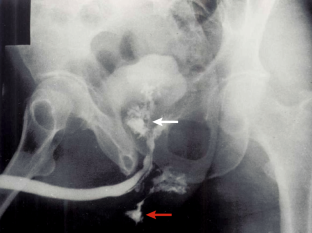

Mayilvaganan, K. R., Naren Satya Srinivas, M., Reddy, V. N. & Singh, R. K. Tuberculosis penis with ‘Watering can penis’ appearance: report of a rare case with retrograde urethrography and voiding cystourethrography findings. Pol. J. Radiol. 81, 454–457 (2016).

Prakash, G. et al. Primary tuberculosis of urethra presenting as stricture urethra and watering can perineum: a rarity. Urol. Ann. 8, 493–495 (2016).